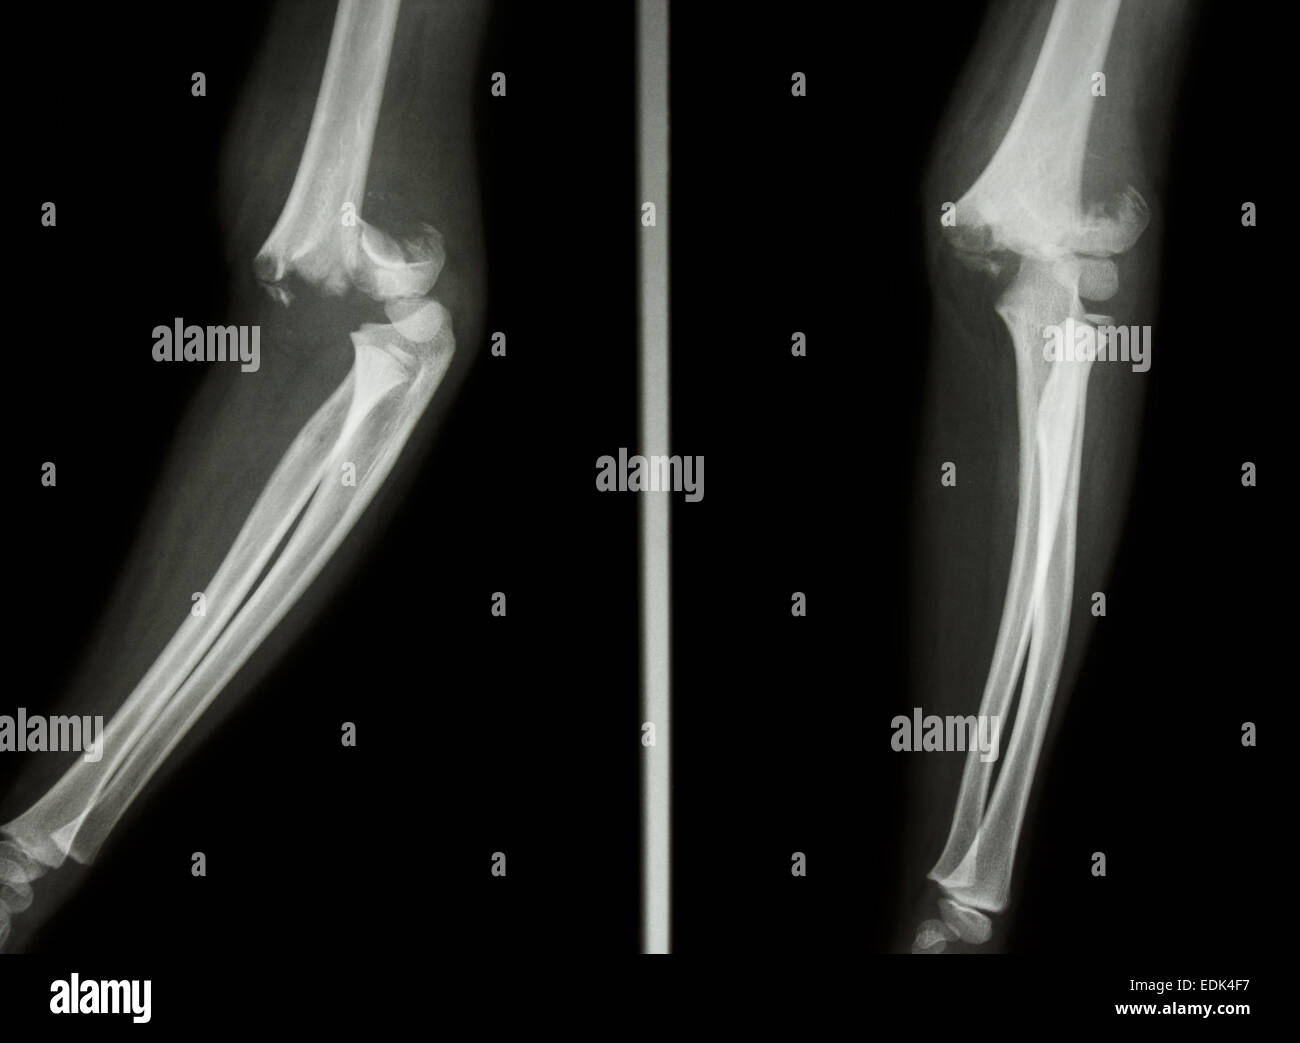

Frattura di condilo femorale. Fratture sovracondiloidee sono il più comune tipo di infortunio al braccio superiore nei bambini.

Una frattura sopracondilare è una lesione allomero o osso superiore del braccio nel punto più stretto appena sopra il gomito. FRATTURA DEL COLLO DEL FEMORE. Frattura di epifisi distale parte non specificata.

Lultimo caso T148 è quello di una frattura sopracondilare di un femore sinistro con neoformazione ossea sulla superficie mediale. Il trattamento di una frattura del femore sopracondilare è altamente variabile e può comportare un cast o un tutore un fissatore esterno una verga intramidollare o luso. Frattura del ginocchio articolare distale La frattura del femore distale nota anche come frattura del femore sopracondilare si trova sullalbero vicino allarticolazione del ginocchio.

Frattura del femore sopracondilare. Frattura prossimale del femore frattura dellanca. È un tipo di infortunio meno frequente e avviene quando qualcuno cade allindietro sul palmo della mano quando il polso è esteso o in alcuni casi quando cè un colpo diretto sullavambraccio.

Notching intaccatura della corticale dorsale del femore frattura del femore sopracondilare. Complicanze elle ratture sovracondiloidee llomero i t diatrica Complication of upracondylar umeral ractures in hildren 260 1 F 2 tena 1 oto 1 O Ortopedia e Traumatologia 2 O irurgia iotruttia e della ano Itituto Giannina Galini Genoa. Una frattura del femore può causare un sanguinamento significativo che può causare shock.

La frattura del ginocchio si può verificare nella rotula condili femorali piatto tibiale eminenza intercondiloidea tibiale e tuberosità tibiale. Una frattura del femore sopracondilare è una condizione problematica in quanto può aumentare il rischio di sviluppare lartrite del ginocchio più avanti nella vita. Quanto vale in termini di danno biologico un soggetto anziano investito sul marciapiede frattura di femore e di Colles che ha perso la capacità di deambulare.